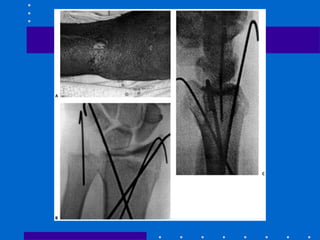

Fixação externa + Pinagem

• Aumenta estabilidade e previne perda de

redução com relação ao FE isolado

• Maior complicação é lesão do nervo radial

superficial

• Fazer incisão de 5 mm e utilizar

hemostática para liberar trajeto

Fixador Externo

Lesão nervosa cutânea

• 16 a 20 % casos

• Disestesias tendem a resolver em 6 meses

• Pode precipitar complexo regional de dor

• Colocar pinos com minincisão diminui

riscos, além de mais dorsal

Infecção de pinos

• Fio de Kirschner : 6 a 33%

• Pinos da fixador externo : 1 a 8 %

• Não se sabe se pré broquear aumenta ou não

risco de infecçao